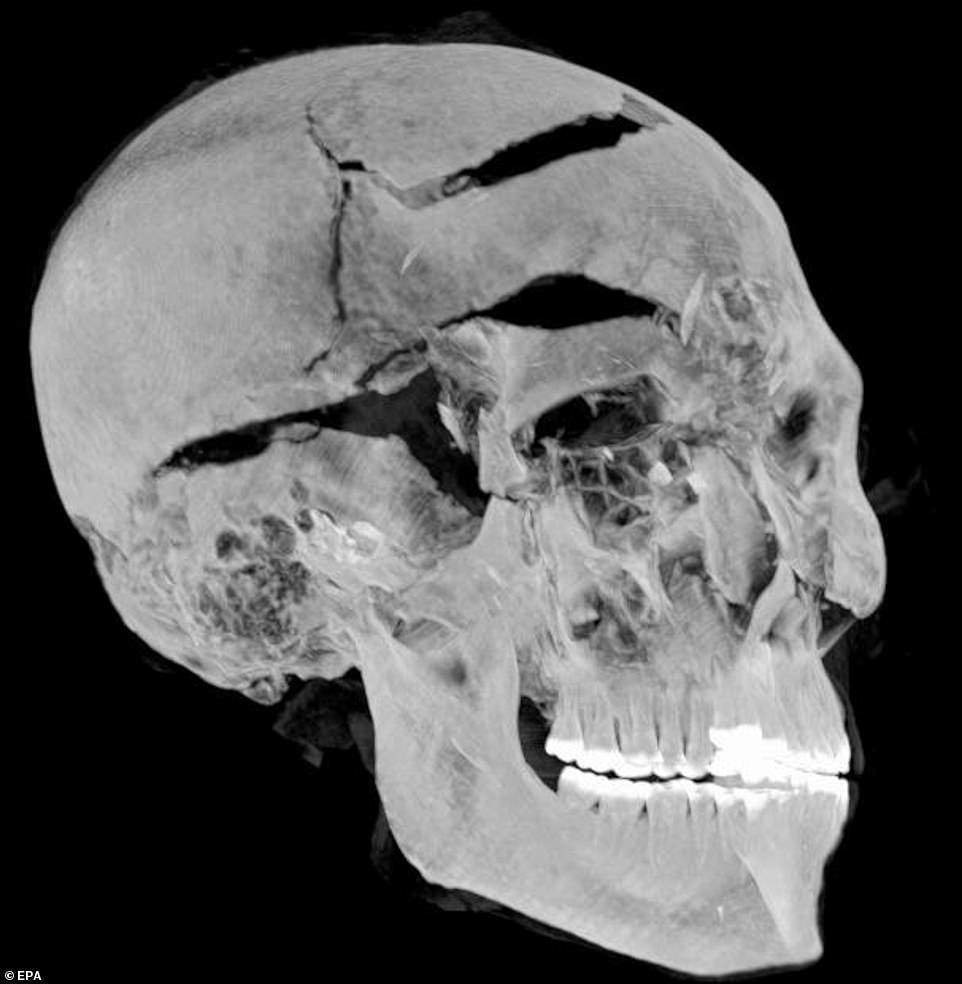

وذكرت صحيفة "ديلى ميل" البريطانية، أن الخبراء المصريين اجروا أشعة مقطعية على مومياء الفرعون سيكننر تاو المعروفة بـ "الشجاع"، وكشفوا عن تفاصيل جديدة حول الإصابات التي أدت إلى وفاته.

وكانت طريقة وفاته موضع نقاش منذ ذلك الحين، حيث أشارت عمليات الفحص البصري والفحص بالأشعة السينية في أواخر الستينيات إلى أن الفرعون تعرض لعدد من الإصابات الشديدة في الرأس.

وتضمنت الاكتشافات من فحوصات التصوير المقطعي آفات لم يتم اكتشافها سابقًا، والتي أخفاها محنطو سقنن رع بمهارة تحت طبقة من المواد، كما يقول الباحثون، وتعمل مثل الحشوات المستخدمة في الجراحة التجميلية الحديثة.

وأشارت صور الأشعة السينية أيضًا إلى أن الفرعون كان يبلغ من العمر 40 عامًا تقريبًا وقت وفاته.

وبناءًعلى النتائج التي توصلوا إليها، توصل الفريق إلى أن سقنن رع قد تم أسره بالفعل في ساحة المعركة، وأن يديه كانت مقيدة خلف ظهره، بحيث لم يكن قادرًا على الدفاع عن نفسه من الهجوم.